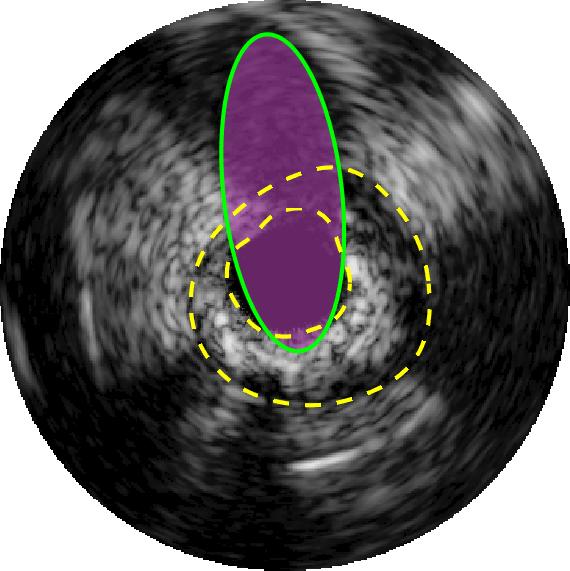

Qualitative evaluations are illustrated in Figure 4 and show the successful segmentation results of the proposed EREL selection strategy for 20 IVUS frames. The lumen areas are highlighted by the magenta colour while the media regions are green. Also, the manually annotated contours for both lumen and media are drawn as yellow dashed lines. As we can see, the chosen frames contain a variety of lumen and media morphologies.